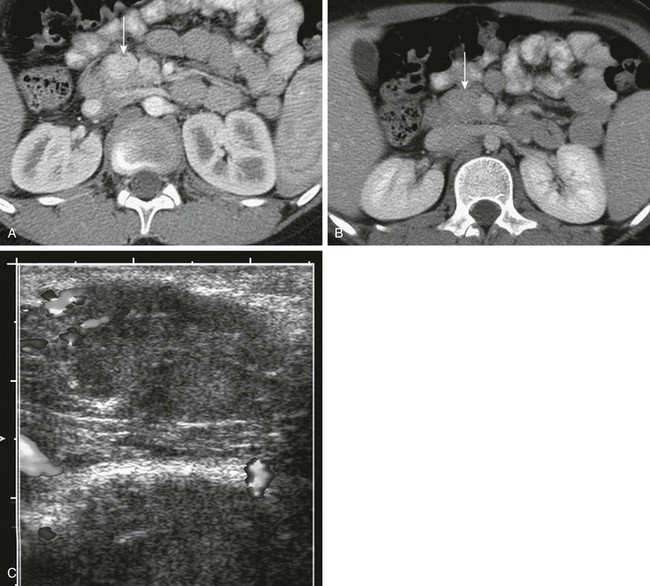

Figure 96-1 Normal pancreas in an 11-year-old boy.

A to C, Computed tomography (CT) sections of the pancreas. The head of the pancreas (arrow in A) is slightly bulbous and distinct from the contrast-filled duodenal sweep. The body of the pancreas (B) is narrower than the head or tail and is seen anterior to the aorta, from which the superior mesenteric artery arises. The tail of the pancreas (C) is thicker in children than in adults and extends to the spleen. D, Transverse ultrasound shows the double track of a normal pancreatic duct.